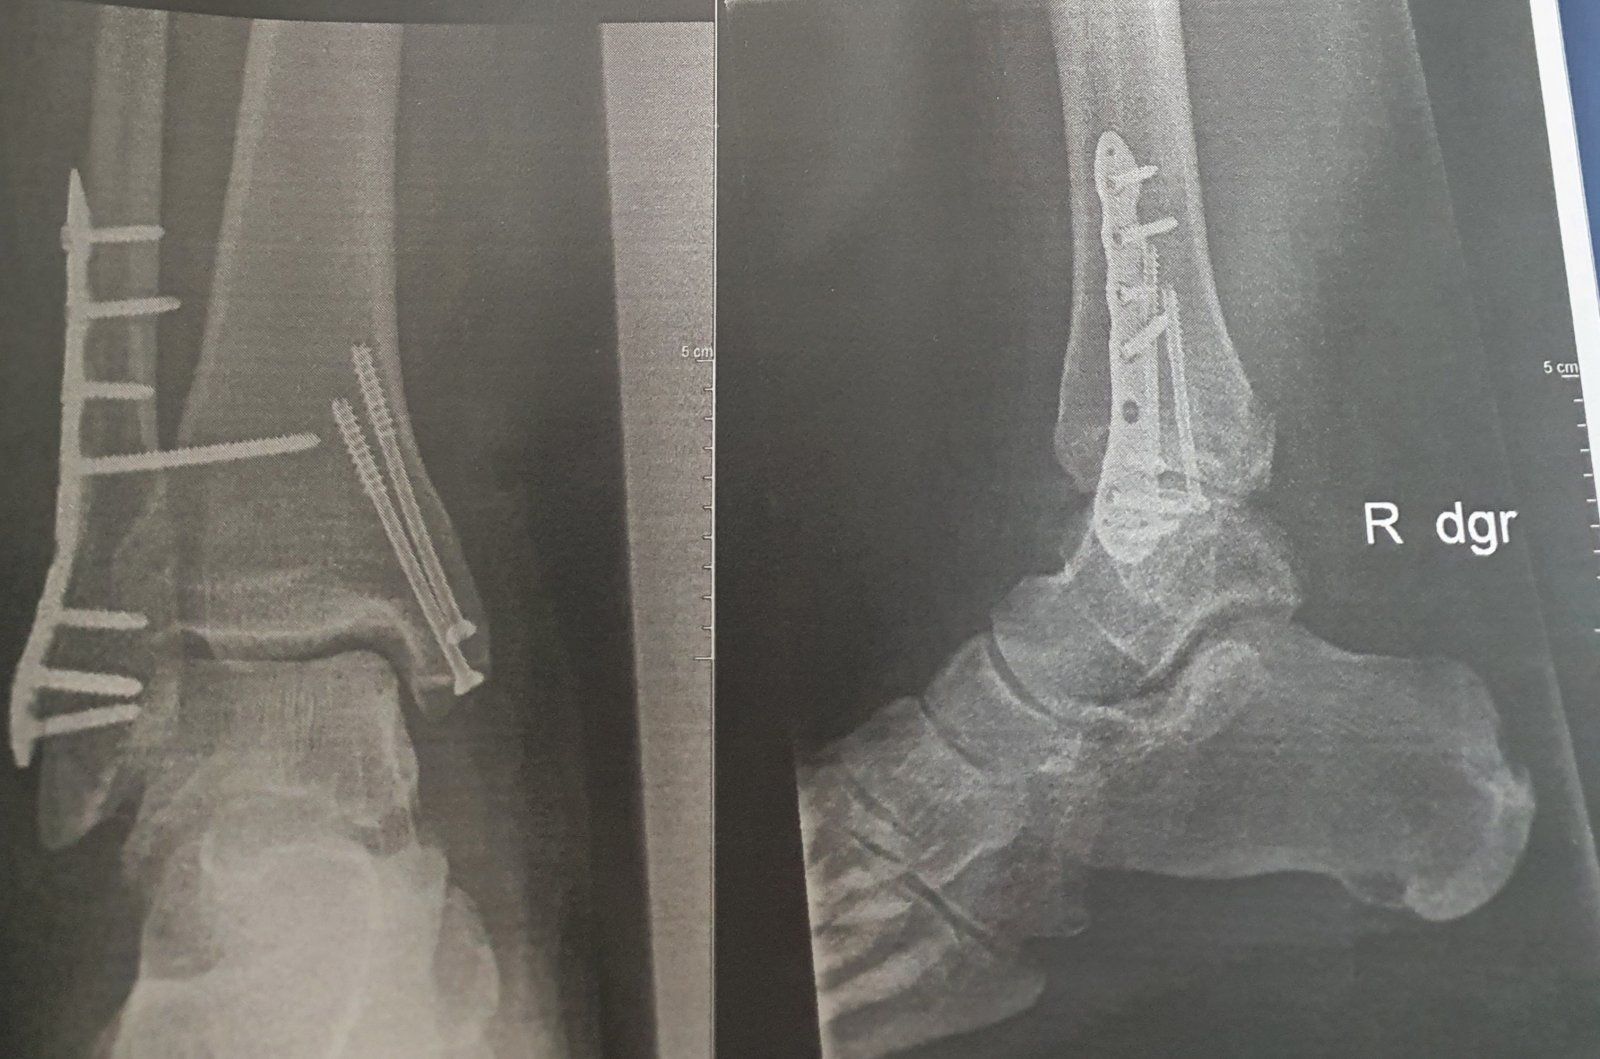

Der Talus war ziemlich zerlegt (Marti u Weber Typ III). Die kleinen Bruchstücke wurden rausgeputzt. Die großen wurden mit 4 Schrauben fixiert. Um ranzukommen musste der Malleolus medialis abgesägt werden und dann wieder mit 2 Schrauben fixiert.

Das Gelenk wurde dann mit Kirschner Draht von unten durch die Ferse ruhiggestellt. 12 Wochen Gips ohne Belastung, nach der 10. Woche wurde der Draht gezogen. Schrauben bleiben drin solang sie keinen Ärger machen.